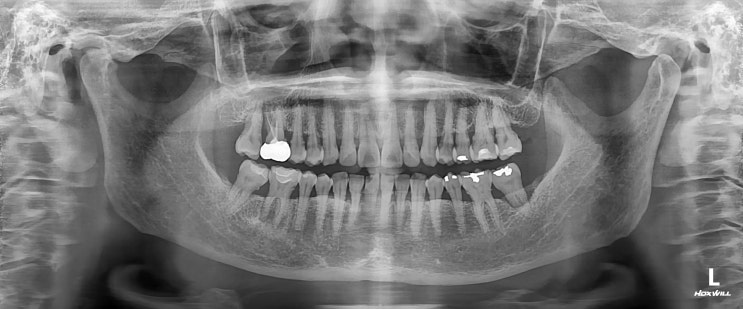

[수서 신혼희망타운 치과] 치근단 염증 신경치료

안녕하세요 수서역치과 수서신혼희망타운 치과 치과 보철과 전문의 이재현입니다 예전에 치근단 염증으로 ...

[헬리오시티 치과] 치아 뿌리 염증 신경치료 후 회복

안녕하세요 수서역치과 문정도 치과 수서서울삼성치과 원장 이재현입니다 오늘은 신경치료 후 회복한 환자...